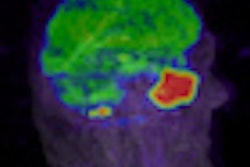

CHICAGO - PET/MRI can outperform PET/CT for lesion conspicuity and characterization in the abdomen, particularly in the liver, according to a study presented by Swiss researchers on Wednesday at the RSNA 2011 meeting.

The preliminary data indicate that PET/MRI "tends to outperform PET/CT in abdominal lesion characterization and conspicuity when using unenhanced CT and MRI, although this difference falls short of statistical significance," Crook and colleagues concluded. The difference, however, is significant in the liver.

Editor's note: The image on the home page is courtesy of the University of Geneva.